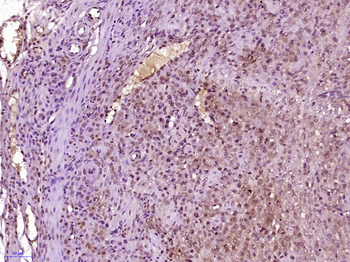

IF, IHC-Fr, IHC-P

应用稀释比例:IHC-P=1:100-500, IHC-F=1:100-500, IF=1:100-500